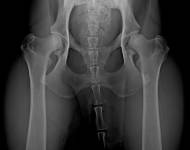

MVDr. Meloun: Lumbosakrální přechodový obratel